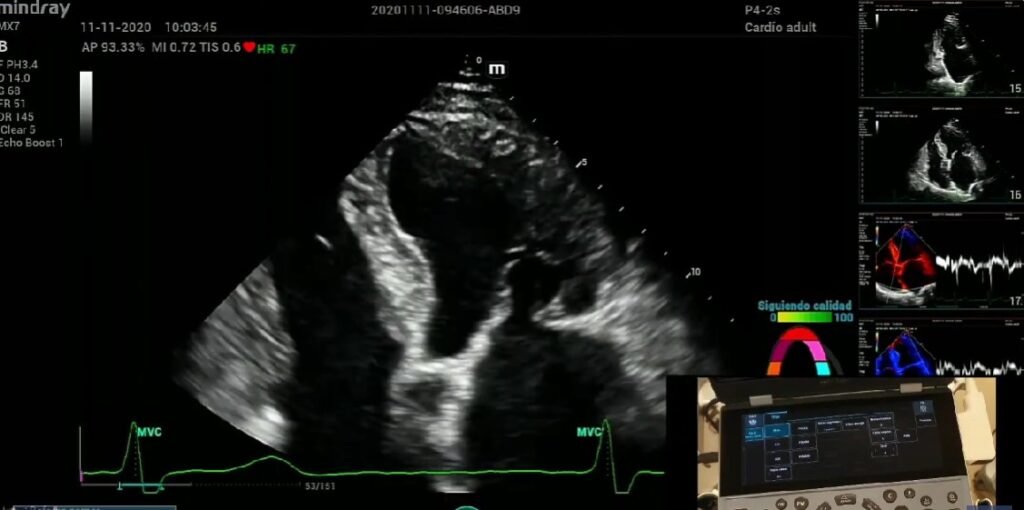

Consiste en el Tamiz cardiaco neonatal ya mencionado en su apartado correspondiente, donde se manifiestan claramente las 6 enfermedades que puede detectar este estudio, dejando la gran mayoría de las enfermedades cardiacas más frecuentes; como lo son la comunicación interauricular, conducto arterioso permeable y la comunicación interventricular sin diagnosticar. Nuestro estudio ampliado considera esta deficiencia observada en el tamiz neonatal, ampliándolo con un Rastreo Ecocardiográfico pediátrico , donde podremos descartar con 4 tomas, mas de 30 enfermedades cardiacas cianógenas y no cianógenas.